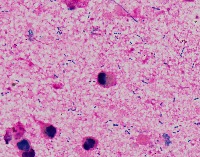

Medical Research: This model can be utilized in the field of medical microbiology and research to classify bacterial strains based on their visual characteristics in lab experiments and for the study of bacterial growth processes.

Healthcare Diagnostics: In healthcare, the "assembly" model could be used to assist in bacterial diagnosis in clinical lab settings, identifying the presence of specific forms of bacteria like Staphylococcus, Streptococcus, B-catarrhalis, Str_pne, and Enterococcus in samples.

Pharmaceutical Industry: The model could be applied in the development stages of antibiotics or bacterial treatments, helping to identify and study the response of specific bacterial strains to new drugs.

Educational Tools: Educators and students could employ the model as a learning tool for illustrating bacterial species classes, supplementing traditional teaching methods in biology or medicine related courses.